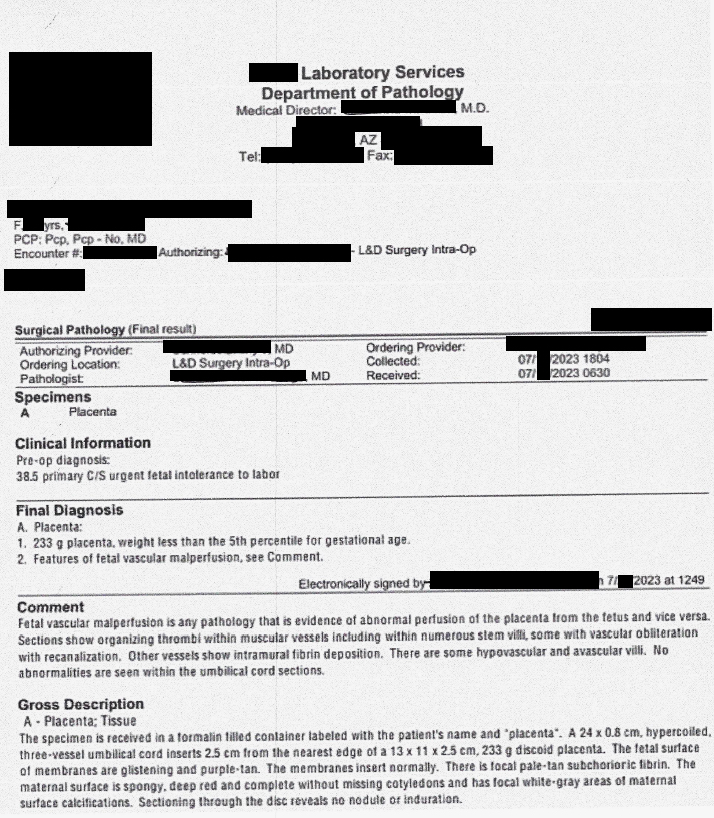

The placenta pathology results were shocking and showed:

- Fetal vascular malperfusion, “…a condition that affects the blood flow in the developing fetus resulting in abnormal fetal development…The signs and symptoms of Fetal Vascular Malperfusion may include excessive hemorrhage during childbirth and decreased blood supply to the fetus, which may affect fetal growth and development.” [https://www.dovemed.com/diseases-conditions/fetal-vascular-malperfusion/]

- “Placental weight of 233 grams (8.21 ounces) less than the fifth percentile for gestational age.” [pathology report] 3.21 ounces is one-third of normal placenta weight at this gestational age. By the time a pregnant woman reaches 39 weeks of pregnancy, the placenta typically weighs about 1.5 pounds or 24 ounces. [https://www.whattoexpect.com/pregnancy/placenta]

- Sections showed “organizing thrombi within muscular vessels including within numerous stem villi, some with vascular obliteration with recanalization.” [pathology report] This placenta had blood clots and compromised blood flow, which leads to increased risk of injury, growth restriction, placental injury, and other harmful outcomes. Key terms to understand are:

- Multiple vessels showing “intramural fibrin deposition,” which are “fibrin or fibrinoid depositions…within the wall of large fetal vessels, with calcification.” [https://www.humpath.com/spip.php?article24614]

- “Hypovascular and avascular villi.”

- “…white-gray areas of maternal surface calcifications.” (These calcifications align with midwife Ellen Jasmer’s testimony about placentas, as well as aligning with maternal-fetal medicine specialist, Dr. James Thorp’s, observations of calcified placenta in his patients.)